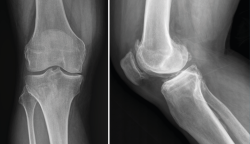

Radiología

El diagnóstico radiológico consiste en la realización de una radiografía sobre una zona del organismo para el estudio de los órganos que se encuentran en su interior.

La radiología es útil para el diagnóstico de las fracturas, luxaciones, osteoartritis o para cuantificar las desviaciones axiales y planificar las cirugías de realineación(1).

Es el procedimiento de imagen empleado generalmente como primera elección y es muy útil para la visualización de los elementos óseos, con la limitación que supone la superposición en un mismo plano de todas las estructuras atravesadas por los rayos X.

Deben hacerse proyecciones anteroposterior (AP) y lateral, generalmente con flexión de 30°, y axial de la rótula cuando se sospeche patología de esta; y proyecciones especiales oblicuas o laterales, proyecciones forzadas de varo o valgo, y AP en 45°, para valorar mejor la interlínea articular(2).

1. Lesiones traumáticas

1.1. Fracturas

1.1.1. Fémur (Figura 1)

Figura 1. Radiografías anteroposterior y lateral de rodilla: fractura longitudinal del fémur extendida a la articulación.